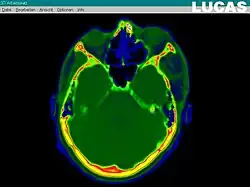

Wichtigster Bestandteil von CAS ist die Entwicklung eines präzisen Modells des Patienten. Dies kann durch bildgebende Verfahren wie Computertomographie, Magnetresonanztomographie, oder Ultraschall geschehen. Die Aufnahmen werden heute in der Regel schon digital erstellt und müssen nicht mehr eingescannt werden. Es ist sinnvoll, mehrere Modalitäten zu kombinieren. Beispielsweise sind MR-Bilder sehr kontrastreich, aber nicht geometrisch genau; CT-Daten sind dagegen strecken- und winkeltreu im Rahmen der Auflösung des verwendeten Scanners. Die Bilder können parallel nebeneinander präsentiert oder optisch überlagert werden (Datenfusion). Die Fusion kann halb- oder vollautomatisch erfolgen. Ziel ist ein 3D-Datasets, der die exakte räumliche Lage der normalen und krankhaft veränderten Gewebe und Strukturen der Zielregion wiedergibt. Die Bildanalyse schließt die Bearbeitung des 3D-Modells des Patienten ein, um die relevanten Informationen zu extrahieren. Durch die unterschiedlichen Kontraststufen der verschiedenen Gewebe kann zum Beispiel ein Modell so geändert werden, dass nur feste Strukturen wie Knochen gezeigt werden, oder aber der Verlauf der Arterien und Venen durch das Gehirn sichtbar ist.

Ein Datensatz kann zum Beispiel Daten von 180 CT-Schichten enthalten, 1 mm dicke Schichten in 1 mm Abstand mit jeweils 512 × 512 Pixel. Die Details sowohl der weichen als auch der festen Gewebestrukturen können automatisch segmentiert und dann optisch getrennt dargestellt, z. B. farblich markiert oder dreidimensional freigestellt werden. Von Hand werden Orientierungspunkte („land marks“) gesetzt, um in der Lage zu sein, zu einem späteren Zeitpunkt den virtuellen Datensatz neu auszurichten und mit der Situation während der Operation abzugleichen (Bildregistrierung).

Professionelle medizinische Betrachtungssoftware (DICOM-Viewer, z. B. OsiriX) kann den segmentierten und markierten Datensatz des Patienten als virtuelles 3D-Modell wiedergeben. Dieses Modell kann rotiert, beschnitten und gefiltert werden, um dem Chirurgen Ansichten aus jedem möglichen Blickwinkel und jeder Tiefe zu liefern. So kann der Chirurg den Fall besser beurteilen und eine genauere Diagnose stellen. Dann wird die chirurgische Intervention geplant und virtuell simuliert, bevor die eigentliche Operation stattfindet. Steht ein Operationsroboter zur Verfügung, wird er nun programmiert, die geplanten Aktionen während des aktuellen chirurgischen Eingriffs durchzuführen.